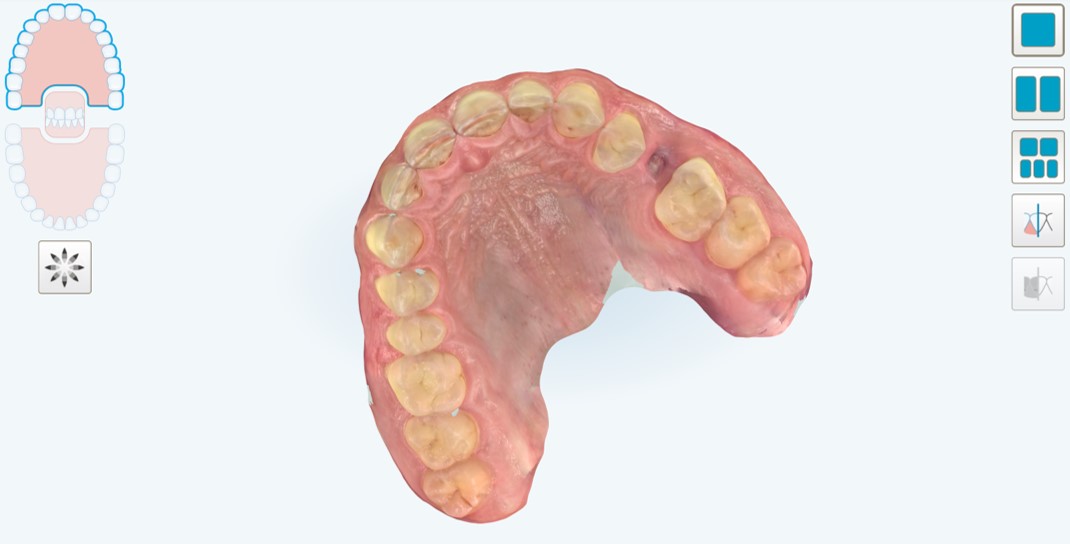

Passato un periodo di tre mesi, necessario al completamento dell’osteointegrazione, si procedeva con la scopertura dell’impianto (Fig. 6) e la cattura della posizione dello stesso attraverso impronta ottica con potente scanner intraorale (Itero Element 5D Plus®, Align Technologies, San Josè, USA). Lo scanbody era one-piece, prodotto in titanio poroso (TQM®, Gioia del Colle, Bari, Italia) (Fig. 7,8,9,10).

impronta ottica con potente scanner intraorale

Fig. 6. A distanza di 3 mesi, è possibile procedere con l’impronta ottica con potente scanner intraorale (Itero Element Plus 5D®, Align Technologies, San Josè, CA, USA). Visione occlusale della vite di guarigione.

Impronta ottica del modello master con il collare mucoso esposto

Fig. 7. Impronta ottica del modello master con il collare mucoso esposto, dopo rimozione dell’healing abutment, e del modello antagonista in masticazione.